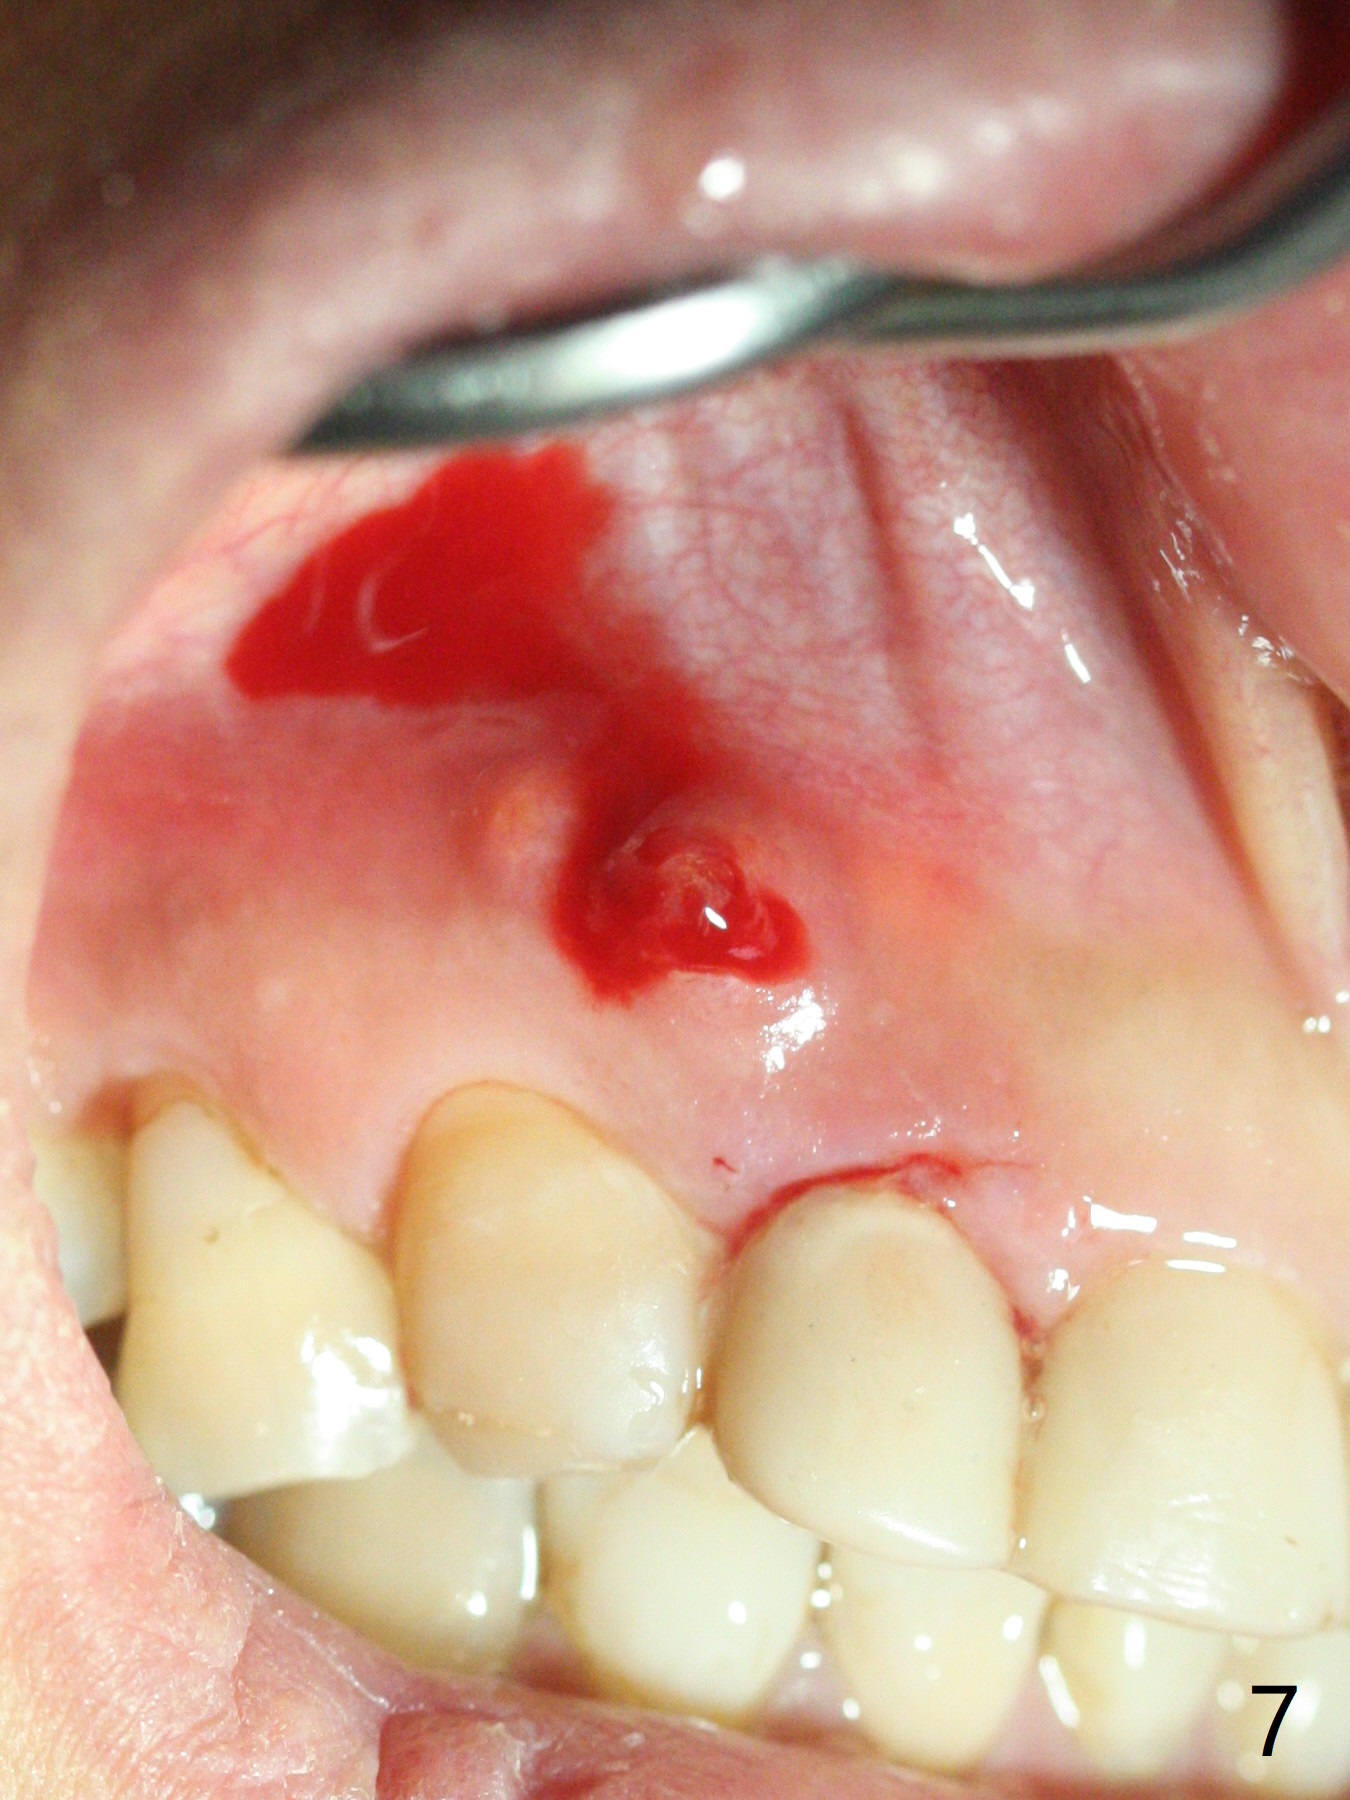

A 47-year-old woman (dental phobic) presented to clinic 9.5 years ago with periapical radiolucency (PARL) at #7 and 9 (Fig.1). RCT was done at #9 because of fistula and symptom 6 months later (Fig.2). While PARL increases at #7 without symptom, that at #9 disappears 8.5 years postop. Three months later, the patient returns for #7 RCT because of the abscesses (Fig.4 *) and pain. Intraop PA is taken with a 30/.06 rotary file in the canal with 19 mm working length (Fig.5). After use of #15 hand file for 20 mm, Ca(OH)2 paste is applied in the canal. When the rubber dam is removed, the abscesses enlarge (Fig.6), which may be related to sodium hypochlorite leakage. A dental explorer is used to try to find a bony opening to the large PARL without success (Fig.7). A postop PA reveals the leakage of Ca(OH)2 paste (Fig.8). Review of the preop PA (Fig.3,9) and intraop PAs (Fig.5,10) shows possible apical resorption and open apical foramen, which is the basis for the paste leakage (Fig.8,11). Careful analysis (with magnification and room light off) of pre- and intra-op PAs should be able to avoid use of #15 hand file out of apical constriction and the complication. The abscess has receded 1 month later (Fig.12). The paste has been resorbed 1 month later (Fig.13). A 30/.06 Gutta Percha is inserted at 18.5 mm (Fig.14 vs. 30/.06 file at 19 mm, 15 file at 20 mm last visit). Fig.15 is the final PA after closure of the access with composite (Fig.15).